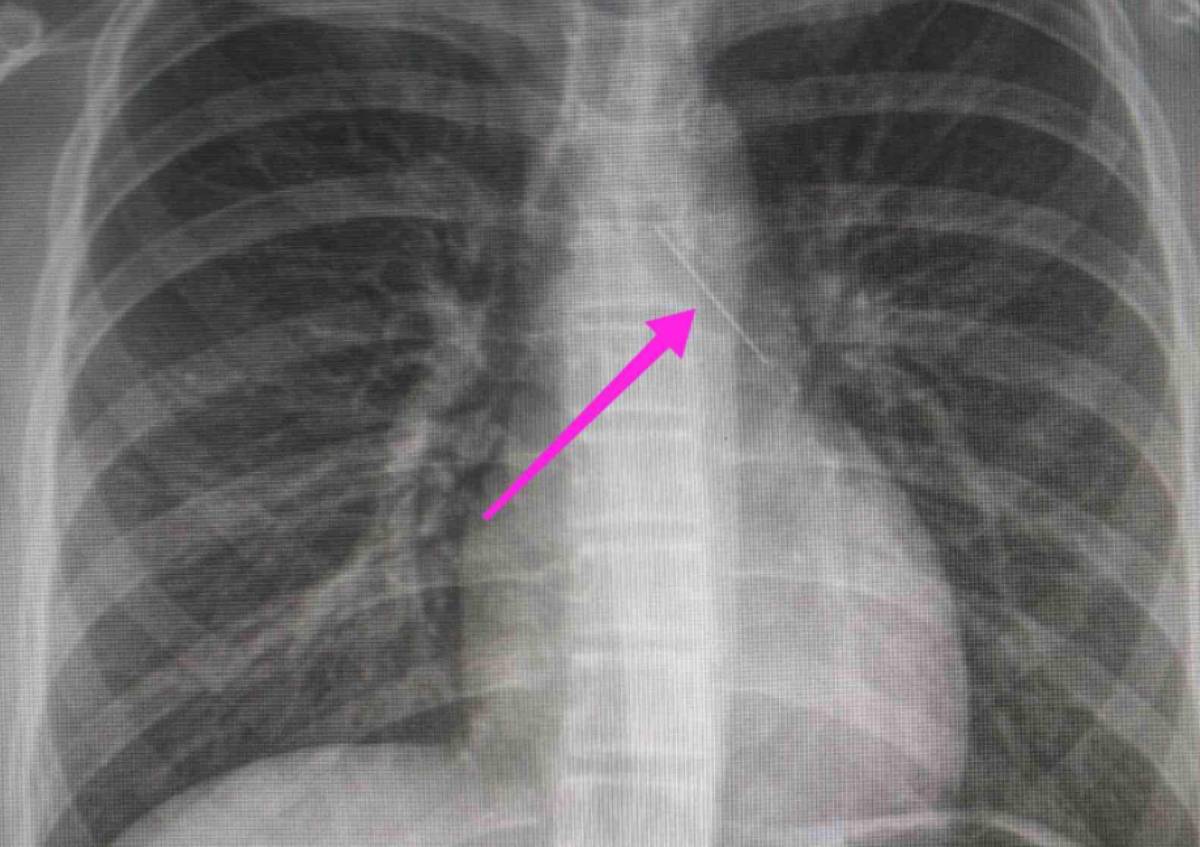

Η καρφίτσα της είχε σταθεί στον δεξιό βρόχγο

Θεσσαλονίκη: Με μια καρφίτσα σφηνωμένη στον δεξιό βρόχγο μεταφέρθηκε την Κυριακή από τους γονείς της στο Ιπποκράτειο Νοσοκομείο Θεσσαλονίκης.

Όπως αναφέρεται στην ανάρτηση του νοσοκομείου, “χθες 30/1/2022 στις 16:00 στο Τ.Ε.Π. του ΓΝΘ Ιπποκράτειο, προσήλθε ανήλικη συνοδευόμενη από τους γονείς της, μετά από αναφερόμενη κατάποση ξένου σώματος (καρφίτσα). Από την απεικονιστική διερεύνηση που πραγματοποιήθηκε με ακτινογραφία θώρακος αρχικά και ακολούθως με αξονική τομογραφία θώρακος, διαπιστώθηκε η ύπαρξη αιχμηρού μεταλλικού ξένου σώματος στην αναπνευστική οδό (αριστερός κύριος βρόγχος) και όχι στην πεπτική οδό.

Κατά την βρογχοσκόπηση διαπιστώθηκε η μετακίνηση και ενσφήνωση του ξένου σώματος στον δεξιό κύριο βρόγχο. Μετά οπό εργώδεις προσπάθειες ολοκληρώθηκε με επιτυχία η αφαίρεση αυτού. Η ασθενής ανένηψε πλήρως εντός της χειρουργικής αίθουσας. Η ασθενής μεταφέρθηκε για παρακολούθηση και νοσηλεία στη Γ’ Παιδιατρική Κλινική.